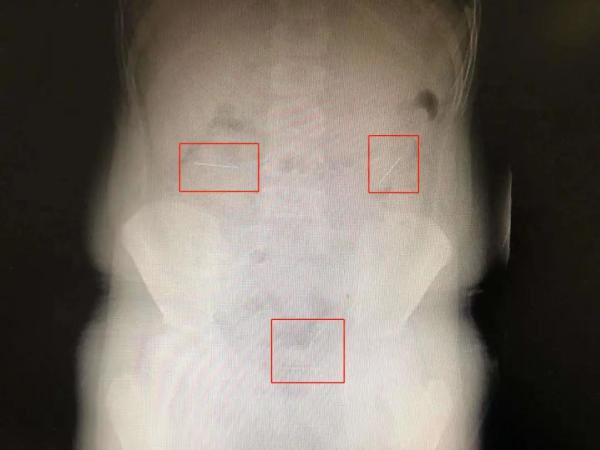

Nghe xong lời trần thuật của con trai, mẹ Lạc Lạc vội vã đưa cậu bé đến bệnh viện. Tại đây, sau khi chụp phim X-quang, các bác sĩ phát hiện phần bụng của Lạc Lạc có 4 "vật thể lạ" giống như kim tiêm.

Những cây kim này đi vào ruột non, qua đường tiêu hóa và đang di chuyển về phía ruột già. Ảnh: Theuntamed

Lạc Lạc, sau đó được chuyển lên Bệnh viện Nhi, Đại học Chiết Giang để điều trị. "Chúng tôi từng gặp một bệnh nhân tương tự, chiếc kim mắc kẹt ở vùng hồi tràng (nơi tiếp giáp của ruột già và ruột non). Người này sau đó phải trải qua một cuộc phẫu thuật. Trong trường hợp của Lạc Lạc, chiếc kim cố định vải có phần đầu tròn, vẫn có khả năng tự đào thải ra ngoài khi phần đầu tròn quay xuống", bác sĩ Cao Chí Cương, trưởng khoa Ngoại tổng quát, Bệnh viện Nhi Đại học Chiết Giang cho biết.

Ông Cao cũng nhận định Lạc Lạc không bị viêm phúc mạc hay thủng ruột  nên trước tiên sẽ thận trọng điều trị, đồng thời chuẩn bị phương án ứng cứu. Trong thời gian cậu bé nằm viện, ông Cao đề nghị Lạc Lạc ăn thêm tỏi tây để thúc đẩy nhu động đường tiêu hóa, giúp những chiếc kim cố định vải có thể ra ngoài theo cách tự nhiên. Đến ngày thứ 5, 4 chiếc kim đều thuận lợi ra ngoài.